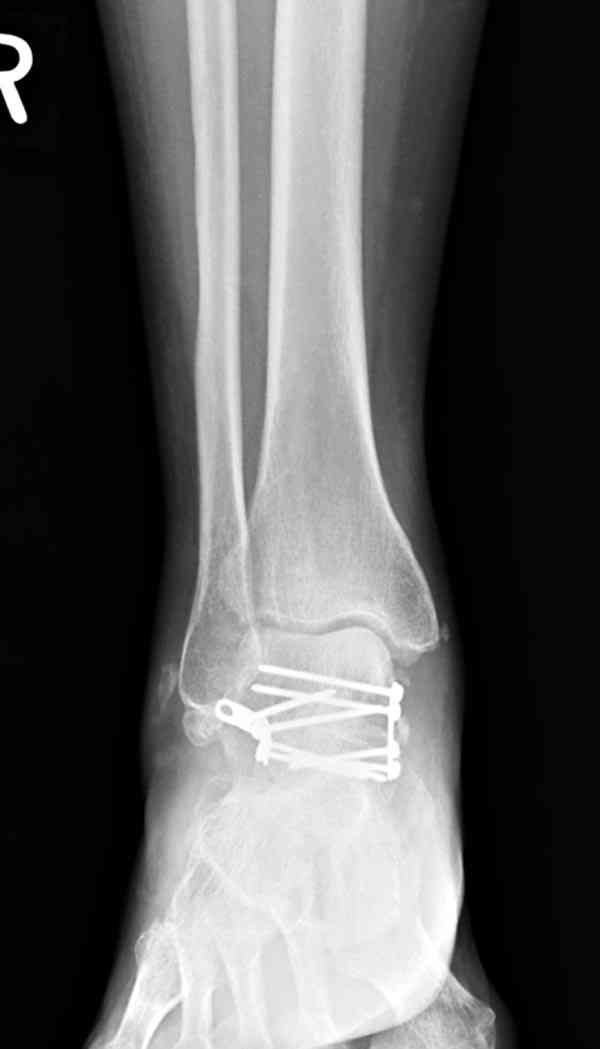

Случай с множественным оскольчатым переломом тарана оперированный из двойного доступа.

Через 2 мес.:

Через 8 мес.:

Через 14 мес.:

Для оценки состояния нужны дополнительные исследования, например

повторили рентгенограммы и доделали проекции, к единому мнению все еще не пришли

На ренгенограмме не уловил многоскольчатость тарана, чтобы доказать, конечно, можно было исследовать на КТ, потом КТ дает ориентацию фрагментов.

Два фрагмента суставной поверхности тарана можно восстановить боковой компрессией шурупами и дополнительно костная пластика.

Решили не связываться с остеосинтезом, а сделать сразу берцово-пяточный блок. Снимки в приложении.

По завершении удлинения, наверно, заштифтуем.

Комментарии/критика приветствуются.